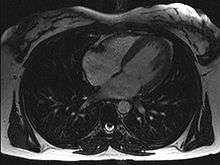

Magnetic resonance imaging

Magnetic resonance imaging (originally called nuclear magnetic resonance imaging), an imaging methodology based on aligning the spin axis of nuclei within molecules of the object being visualized using both powerful superconducting magnets and radio frequency signals and detectors. Cardiology uses are growing, especially since MRI differentiates soft tissues better than CT and allows for comprehensive exams including the quantitative assessment of size, morphology, function, and tissue characteristics in one single session. Current implementations for Cardiology uses are sometimes limited by lengthy protocols, claustrophobia and contraindications based on some complex metallic implants (pacemakers, defibrillators, insulin pumps), while artificial valves and coronary stents are generally not problematic. Image quality can be reduced by the continuous movement of heart structures. There is a promising future in cardiac MRI by more efficient scans, increasing availability of scanners and more widespread knowledge about its clinical application.